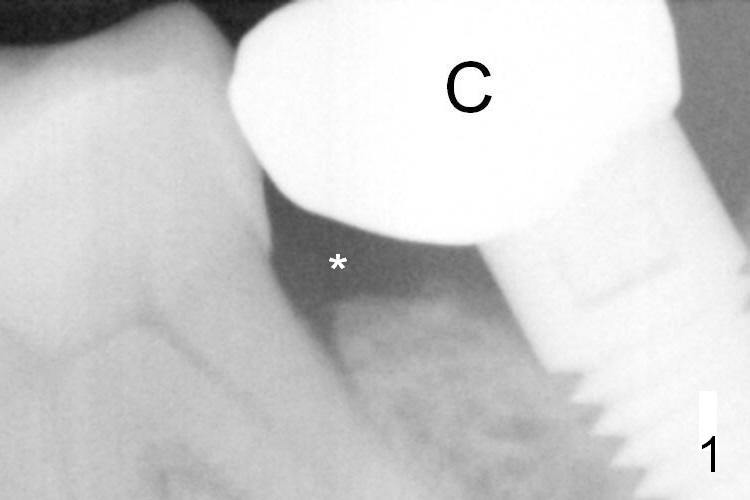

A 65-year-old woman was pleased with functionality of the implant crown at #18 immediately post cementation (Fig.1 (taken 6 months post cementation). In 2 years and 8 months, she complains of gingival irritation after food impaction. Although the proximal contact is slightly light with floss, the gingival embrasure feels to be extremely large (Fig.1 *). When the crown is to be remade, increase the vertical contact (Fig.2 red line) to close the gingival embrasure as much as possible. PA taken immediately before redo shows that there is no gap between #18 and 19 (Fig.3). When the crown is being cut off, the gingiva is tender. It appears that the existing crown (made by Classic Craft) has overextended margin. When the new crown is being fabricated, trim the margin of the die very well. The margin of the new crown should be shorter (Fig.3 red curved line).